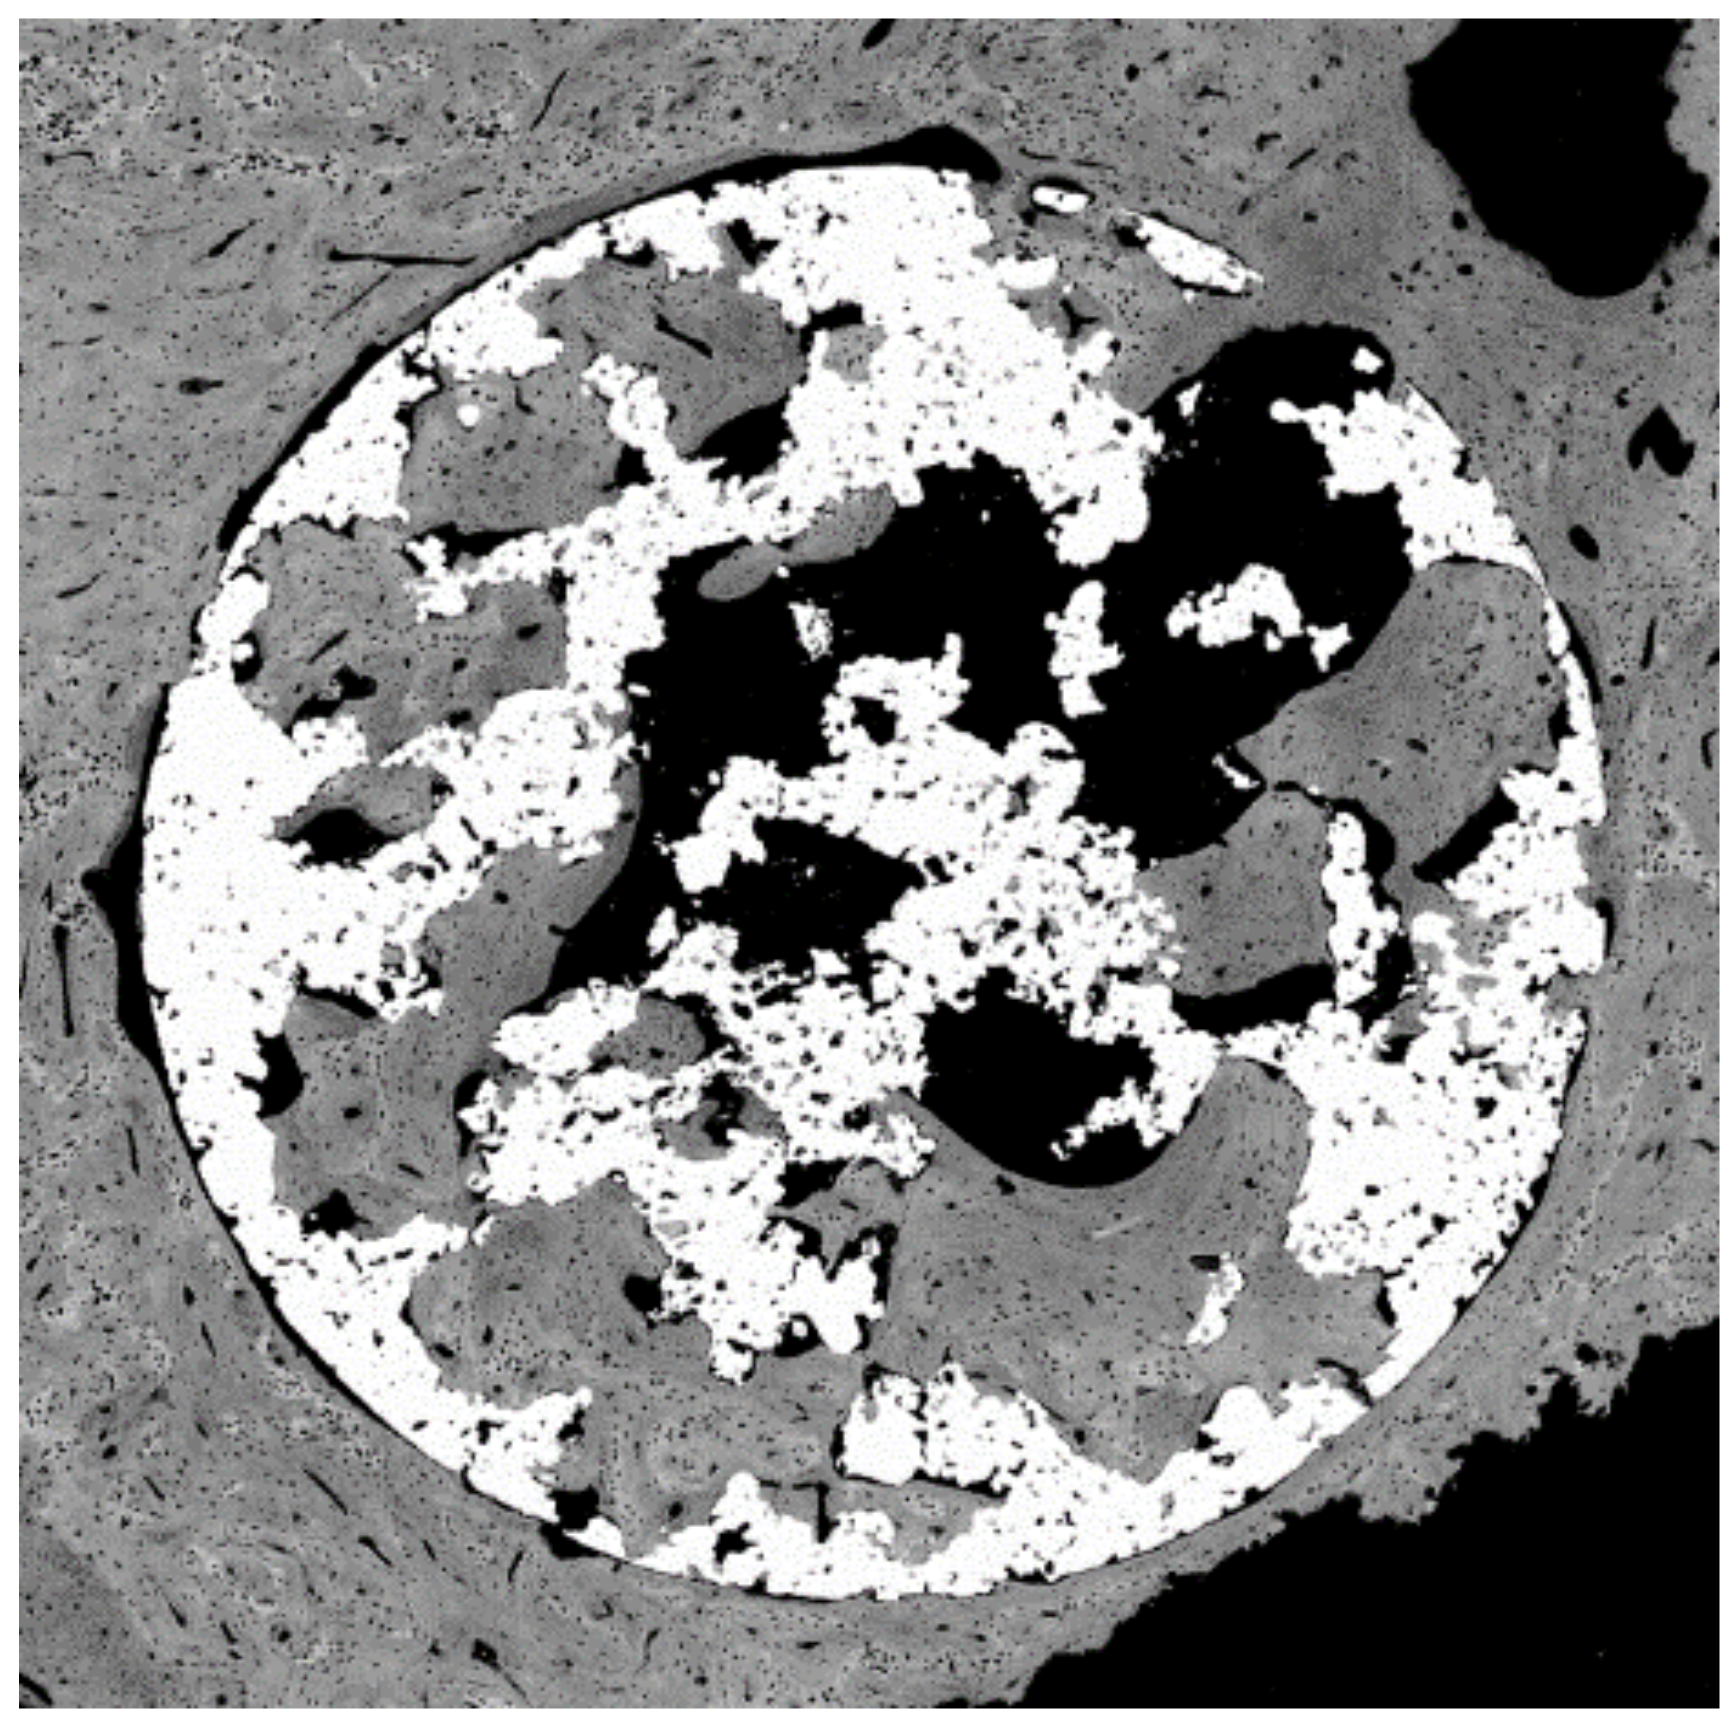

Since the spheres or porous materials obtained are composed of titanium, thermo-chemical treatments have been successfully carried out to obtain the sodium titanate layers that allow the formation of apatite in contact with the physiological medium, accelerating the mineralization process; therefore, the bone colonization will be faster. It was observed that the titanate layer obtained by the treatment is introduced in all the holes and channels of the implant; therefore, the material will have a high osteoconductive-specific surface for bone formation. This finding can be observed in Figure 16. Figure 17 shows a porous titanium material with thermo-chemical treatment in which the colonization and formation of new bone inside the pores of a dental implant can be observed.

Figure 17. Colonization of bone inside the porous of a bioactive porous dental implant.